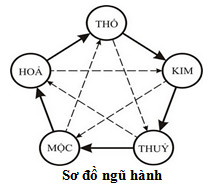

Ngũ hành và sức khỏe

Một trong những phương pháp rất nhanh và hữu hiệu nhất để nhận biết và cải thiện tình trạng sức khỏe là áp dụng thuyết Ngũ hành trong Y lý Đông Phương với hai nguyên lý Tương sinh và Tương khắc.